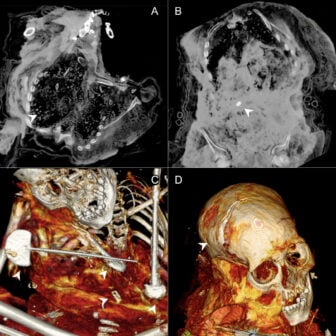

CT scans of Ampato #1, also known as the Lady of Ampato, unveiled injuries in her cranium and the areas of her pelvis and chest. The trauma to the head and pelvis would have been deadly. She died at around 14 years old, her body naturally mummified from the freezing conditions. Her remains were discovered along with little bags of corn, pottery fragments, and figurines.

Ampato #2 met her ritual end when she was around eight years old, also via a terrible head injury. Notably, the CT analyses suggested she had lasting health issues, challenging historical texts indicating the kinds of children that were sacrificed.

Ampato #4, who died at around 10 years old from a (you guessed it) deadly head injury, also revealed something surprising: It appears that her body was intentionally modified after she died and may have even been buried twice. The team identified rocks and pieces of textiles in her abdominal cavity and some missing bones. That makes Ampato #4 the first deliberately mummified capacocha victim known to science.

As for the Sara Sara mummy, she was around 14 years old and experienced cranial injuries comparable to Ampato #1, which means she was probably also a victim of a capacocha. Her remains were naturally mummified and also revealed similar health issues to Ampato #2.